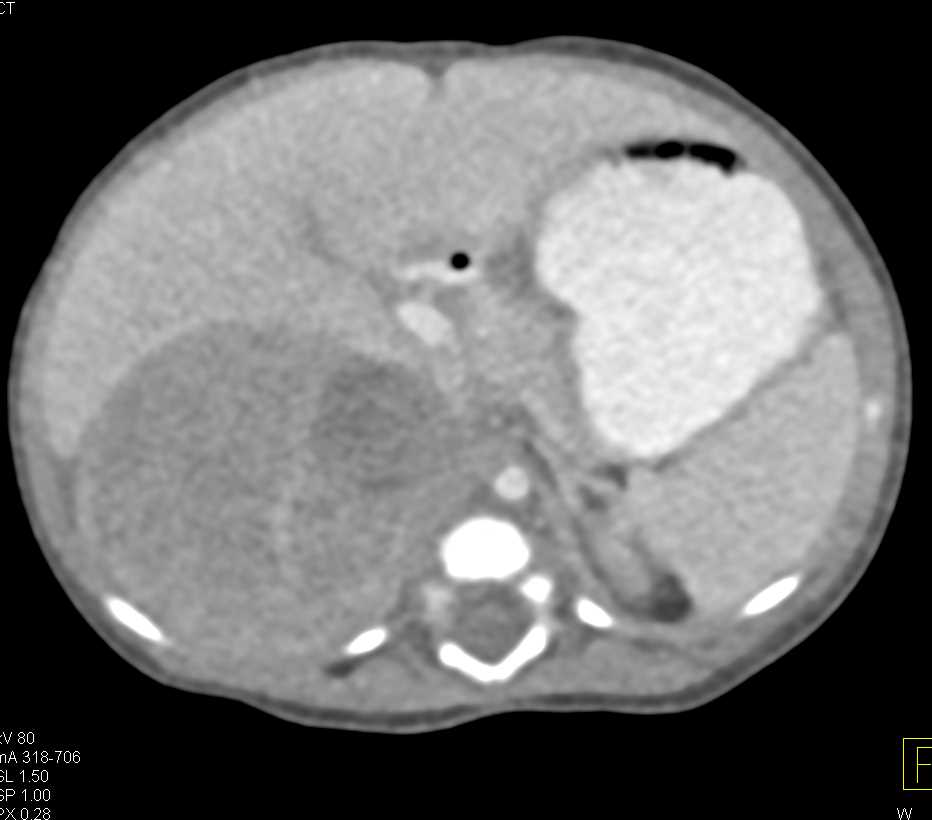

Right Adrenal Pheochromocytoma